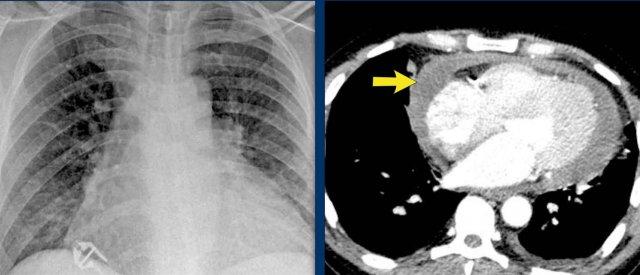

Ca Lâm Sàng 1: Tràn Dịch Màng Ngoài Tim Giả Tim To

- Trên phim X-quang ngực, bệnh nhân có vẻ như bị giãn tim.

- Tuy nhiên, hình ảnh CT cho thấy rõ ràng rằng sự to ra bề ngoài này là do tích tụ dịch màng ngoài tim đáng kể, chứ không phải do giãn buồng cơ tim thực sự.

Ca Lâm Sàng 2 – Hình ảnh CT

- CT cho thấy tràn dịch màng ngoài tim sau lượng lớn đang chèn ép thất trái (mũi tên xanh dương: dịch tràn; mũi tên đỏ: thất trái bị chèn ép, có ngấm thuốc cản quang).

- Phẫu thuật thám sát xác nhận khối máu tụ màng ngoài tim sau lớn.

Lưu ý: Lượng dịch tối thiểu ở phía trước trên siêu âm có thể đánh giá thấp thể tích thực sự nếu dịch tràn khu trú ở phía sau, nhấn mạnh giá trị của CT trong các trường hợp sau phẫu thuật.